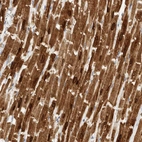

Immunohistochemistry analysis in human heart muscle and placenta tissues using HPA026900 antibody. Corresponding PLN RNA-seq data are presented for the same tissues.